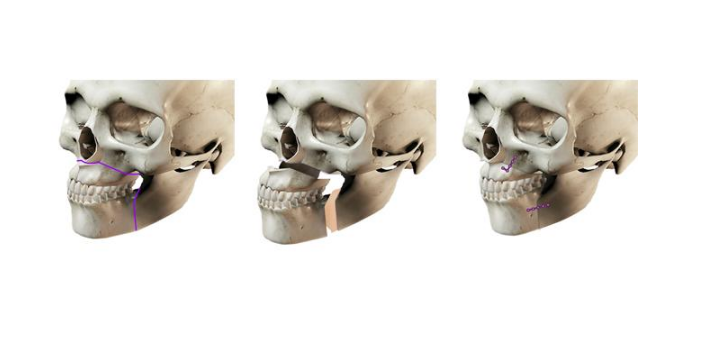

牙顎畸形圖片

牙槽骨突出

牙槽骨突出

牙槽骨突出

牙槽骨突出

牙槽骨突出

牙槽骨突出

牙槽骨突出

牙槽骨突出

牙槽骨突出

牙槽骨突出

牙槽骨突出

牙槽骨突出

牙槽骨突出

牙槽骨突出

牙槽骨突出

牙槽骨突出

牙槽骨突出

牙槽骨突出

牙槽骨突出

牙槽骨突出